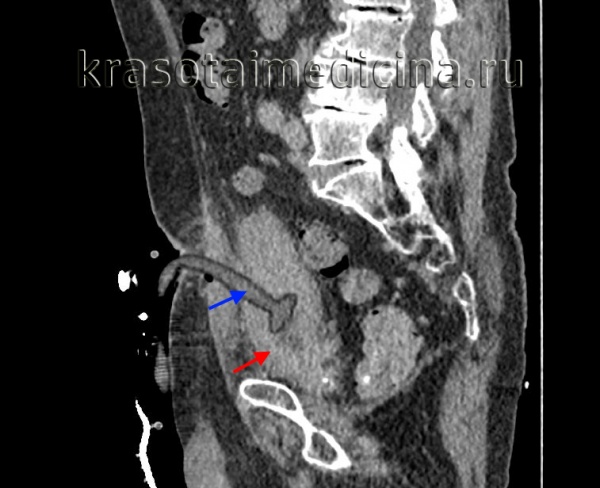

КТ-урографія. Виражене нерівномірне потовщення стінки сечового міхура (червона стрілка) за рахунок хронічного циститу, стан після эпицистостомии, установки надлобкового катетера (синя стрілка).